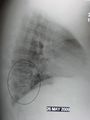

A chest X-ray showing a very prominent wedge shaped pneumonia in the right lung. | |